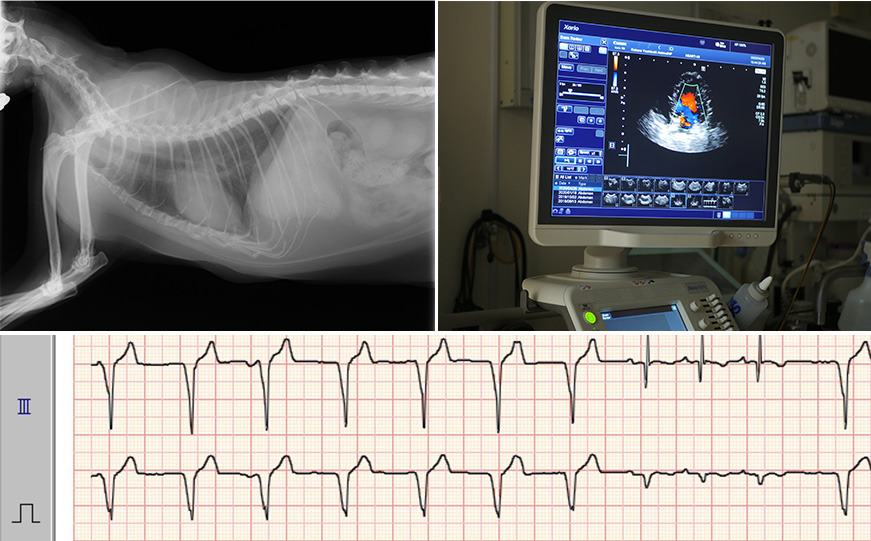

確実な診断を行います。

レントゲン・エコー(超音波検査)・心電図検査など各種先進機器による精密な検査をもとに、エビデンスに基づいた診断、治療を行っています。